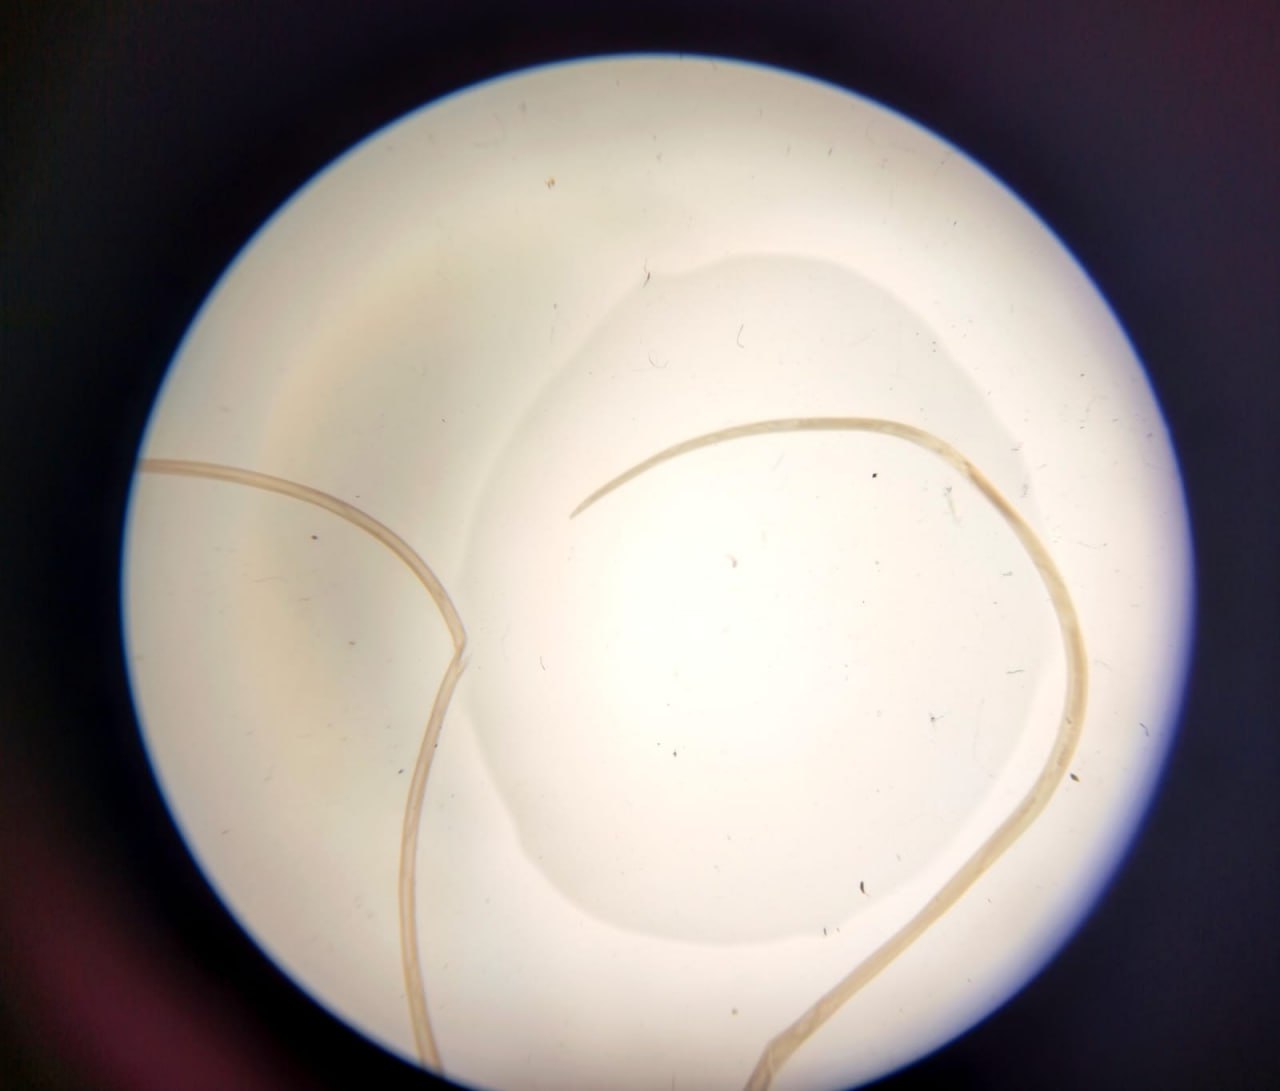

По данным областного центра контроля и профилактики болезней Минздрава, женщина обратилась из-за отека и боли в области век. В ходе осмотра медики обнаружили паразита вида Dirofilaria и удалили его хирургически.

У жительницы Запорожья врачи обнаружили под кожей ужасного паразита. Фото: ЦУПХ